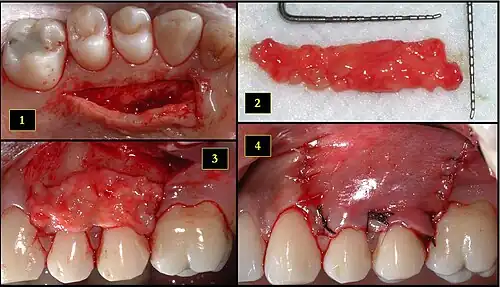

- Ipsilateral palatal mucosa serving as the donor site

- The retrieved connective tissue, approximately 25 × 6 mm in dimension

- Connective tissue placed at recipient site

- Recipient site flap coronally advanced and sutured to entirely cover the graft